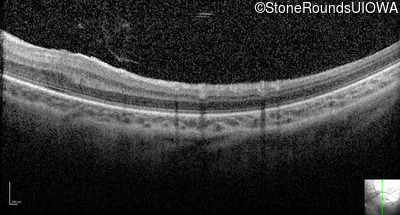

Optical Coherence Tomography - Right - 20/2000

Exemplar / OCT Stack